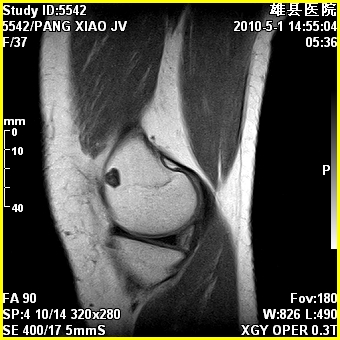

标题: MRI2894:患者右膝关节疼痛两月余,无明显外伤史 [打印本页]

标题: MRI2894:患者右膝关节疼痛两月余,无明显外伤史

右股骨下端前内侧类圆形异常信号,位于干骺端,呈长t1长t2改变,但信号不均,t1图上病灶中心见小片状稍高信号影,t2图上见散在稍低信号影,stir像呈高信号,因病灶较小,缺乏特征性改变,结合患者年龄及部位,考虑嗜酸性肉芽肿可能性大。胫骨关节面下的小囊状异常信号,如果一元论考虑则为嗜酸性肉芽肿,不过发生在这个部位的少见,二元论考虑为邻关节骨囊肿。半月板与前后交叉韧带均未见异常。

右股骨下端前内侧干骺端囊性良性病变,考虑 1内生软骨瘤 2骨囊肿 3肉芽肿。